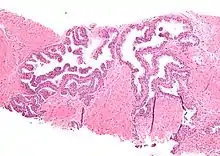

| Micrograph showing high-grade prostatic intraepithelial neoplasia. H&E stain. | |

HGPIN typically has one of four different histologic patterns:[2]

- tufted (fascicular patterning)

- micropapillary,

- cribriform and,

- flat.

Its cytologic features are that of prostatic adenocarcinoma:

- presence of nucleoli,

- increased nuclear-to-cytoplasmic ratio and,

- increased nuclear size.

Microscopically, PIN is a collection of irregular, atypical epithelial cells. The architecture of the glands and ducts remains normal. The epithelial cells proliferate and crowding results in a pseudo-multilayer appearance. They remain fully contained within a prostate acinus (the berry-shaped termination of a gland, where the secretion is produced) or duct. The latter can be demonstrated with special staining techniques (immunohistochemistry for cytokeratins) to identify the basal cells forming the supporting layer of the acinus. In prostate cancer, the abnormal cells spread beyond the boundaries of the acinus and form clusters without basal cells. In HGPIN, the basal cell layer is disrupted but present. PIN is primarily found in the peripheral zone of the prostate (75-80%), rarely in the transition zone (10-15%) and very rarely in the central zone (5%), a distribution that parallels the zonal distribution for prostate carcinoma.[7]

Several architectural variants of PIN have been described, and many cases have multiple patterns. The main ones are tufting, micropapillary, cribriform, and flat. Although these different appearances may cause confusion with other conditions, they have not been found to be of clinical importance. Rarer types are signet-ring-cell, small-cell-neuroendocrine, mucinous, foamy, inverted, and with squamous differentiation.[3]